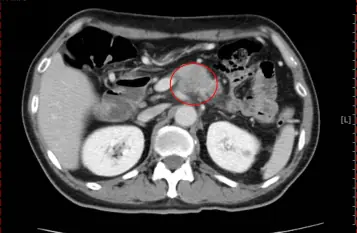

林幸宜主任表示,因患者有膽囊結石病史和飲酒習慣,便安排腹部超音波檢查,報告顯示有膽囊結石,但並未造成膽囊發炎,而抽血檢查結果顯示CA19-9 (檢測胰臟癌等腫瘤標記)數值高達718.92 u/ml(正常值通常小於37 u/ml),再經腹部電腦斷層檢查,發現胰臟體部有一團約3.5公分大腫瘤,診斷是胰臟癌。

圖:患者經腹部電腦斷層檢查,發現胰臟體部有一團約3.5公分大腫瘤(紅圈),診斷是胰臟癌。(澄清醫院提供)